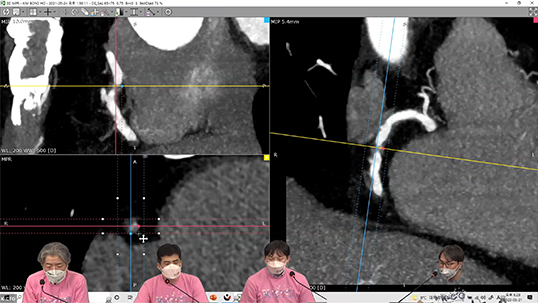

K-CTO club에서 코로나 판데믹 상황에 발맞추어 기획한 온라인 웨비나, 그 세 번째 행사가 2022년3월 21일 월요일 성황리에 열렸습니다. 3회 째를 맞이하면서 참여자도 역대 최다인 248명이 참가하여 꾸준히 참가인원이 증가 하였습니다. 온라인 학회 환경에서 CTO 증례에 대한 좀 더 실제적이고 활발한 토의가 이루어지도록 기획이 된 만큼 다양한 형태의 강의가 이루어 지고 있습니다. 이재환 학술이사 (세종충남대학교병원) 그리고 김병극 총무이사 (연세대학교 신촌세브란스병원) 국형돈 총무보 (한양대학교 병원)가 온라인 moderator로서 활발하게 온라인과 오프라인을 넘나들며 질문과 토론을 이끌었으며 라이브 채팅과 돌발퀴즈를 통한 온라인 참석자와의 활발한 참여도 함께 이루어졌습니다. 이번 웨비나에서는 신상훈 교수님 (이대서울병원)께서 ‘CT coronary angiography 분석하기, From A to Z’를 통해서 시술 전 영상 획득 및 이미지 구성방법에 대해서 프로그램 소개부터 분석방법까지 노하우를 전수해 주셨습니다. 또한 김찬준 교수님 (의정부성모병원)께서 ‘의도되지 않은 투자’란 흥미로운 제목의 케이스를 상세히 소개해 주셨습니다. 앞으로도 이어질 K-CTO Club 온라인 웨비나에 많은 관심과 참여를 부탁 드립니다.